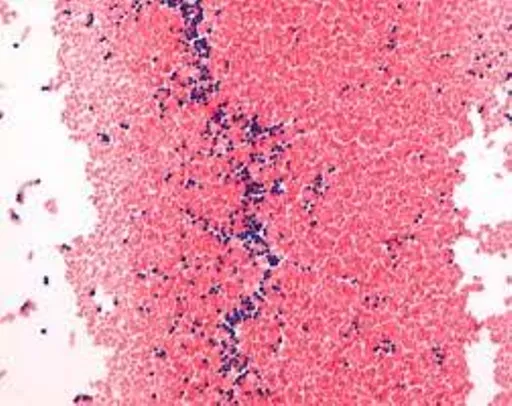

Gram-color staining kit, containing 500 ml each of crystal violet solution, Lugol's solution stabilised, Safranin solution and 2× 500 ml decolourisation solutions.

In bacteriology, the Gram staining allows a fast differentiation of bacteria in Gram-positive and Gram-negative. The mureine structure of the bacteria wall is the basis of the color affinity. In the first step, bacteria will be stained with crystal violet, an aniline dye. After the treatment with iodine solution (Lugol’s solution), a dye-iodine complex will form. During the decolorizing step, this complex stays in the multilayer mureine structure of the cell wall of Gram-positive bacteria - they will appear blue. Gram-negative bacteria have a monolayer mureine structure, the dye-iodine complex does not stay bound to the cell wall - they will be decolorized. Gram-negative bacteria will be counterstained with safranin solution and will then appear orange. The Gram-color stain set contains 5x 500 ml safe PE-bottles and is sufficient for staining up to 250 slides. It fulfills all quality requirements for IVD registration and CE certification.